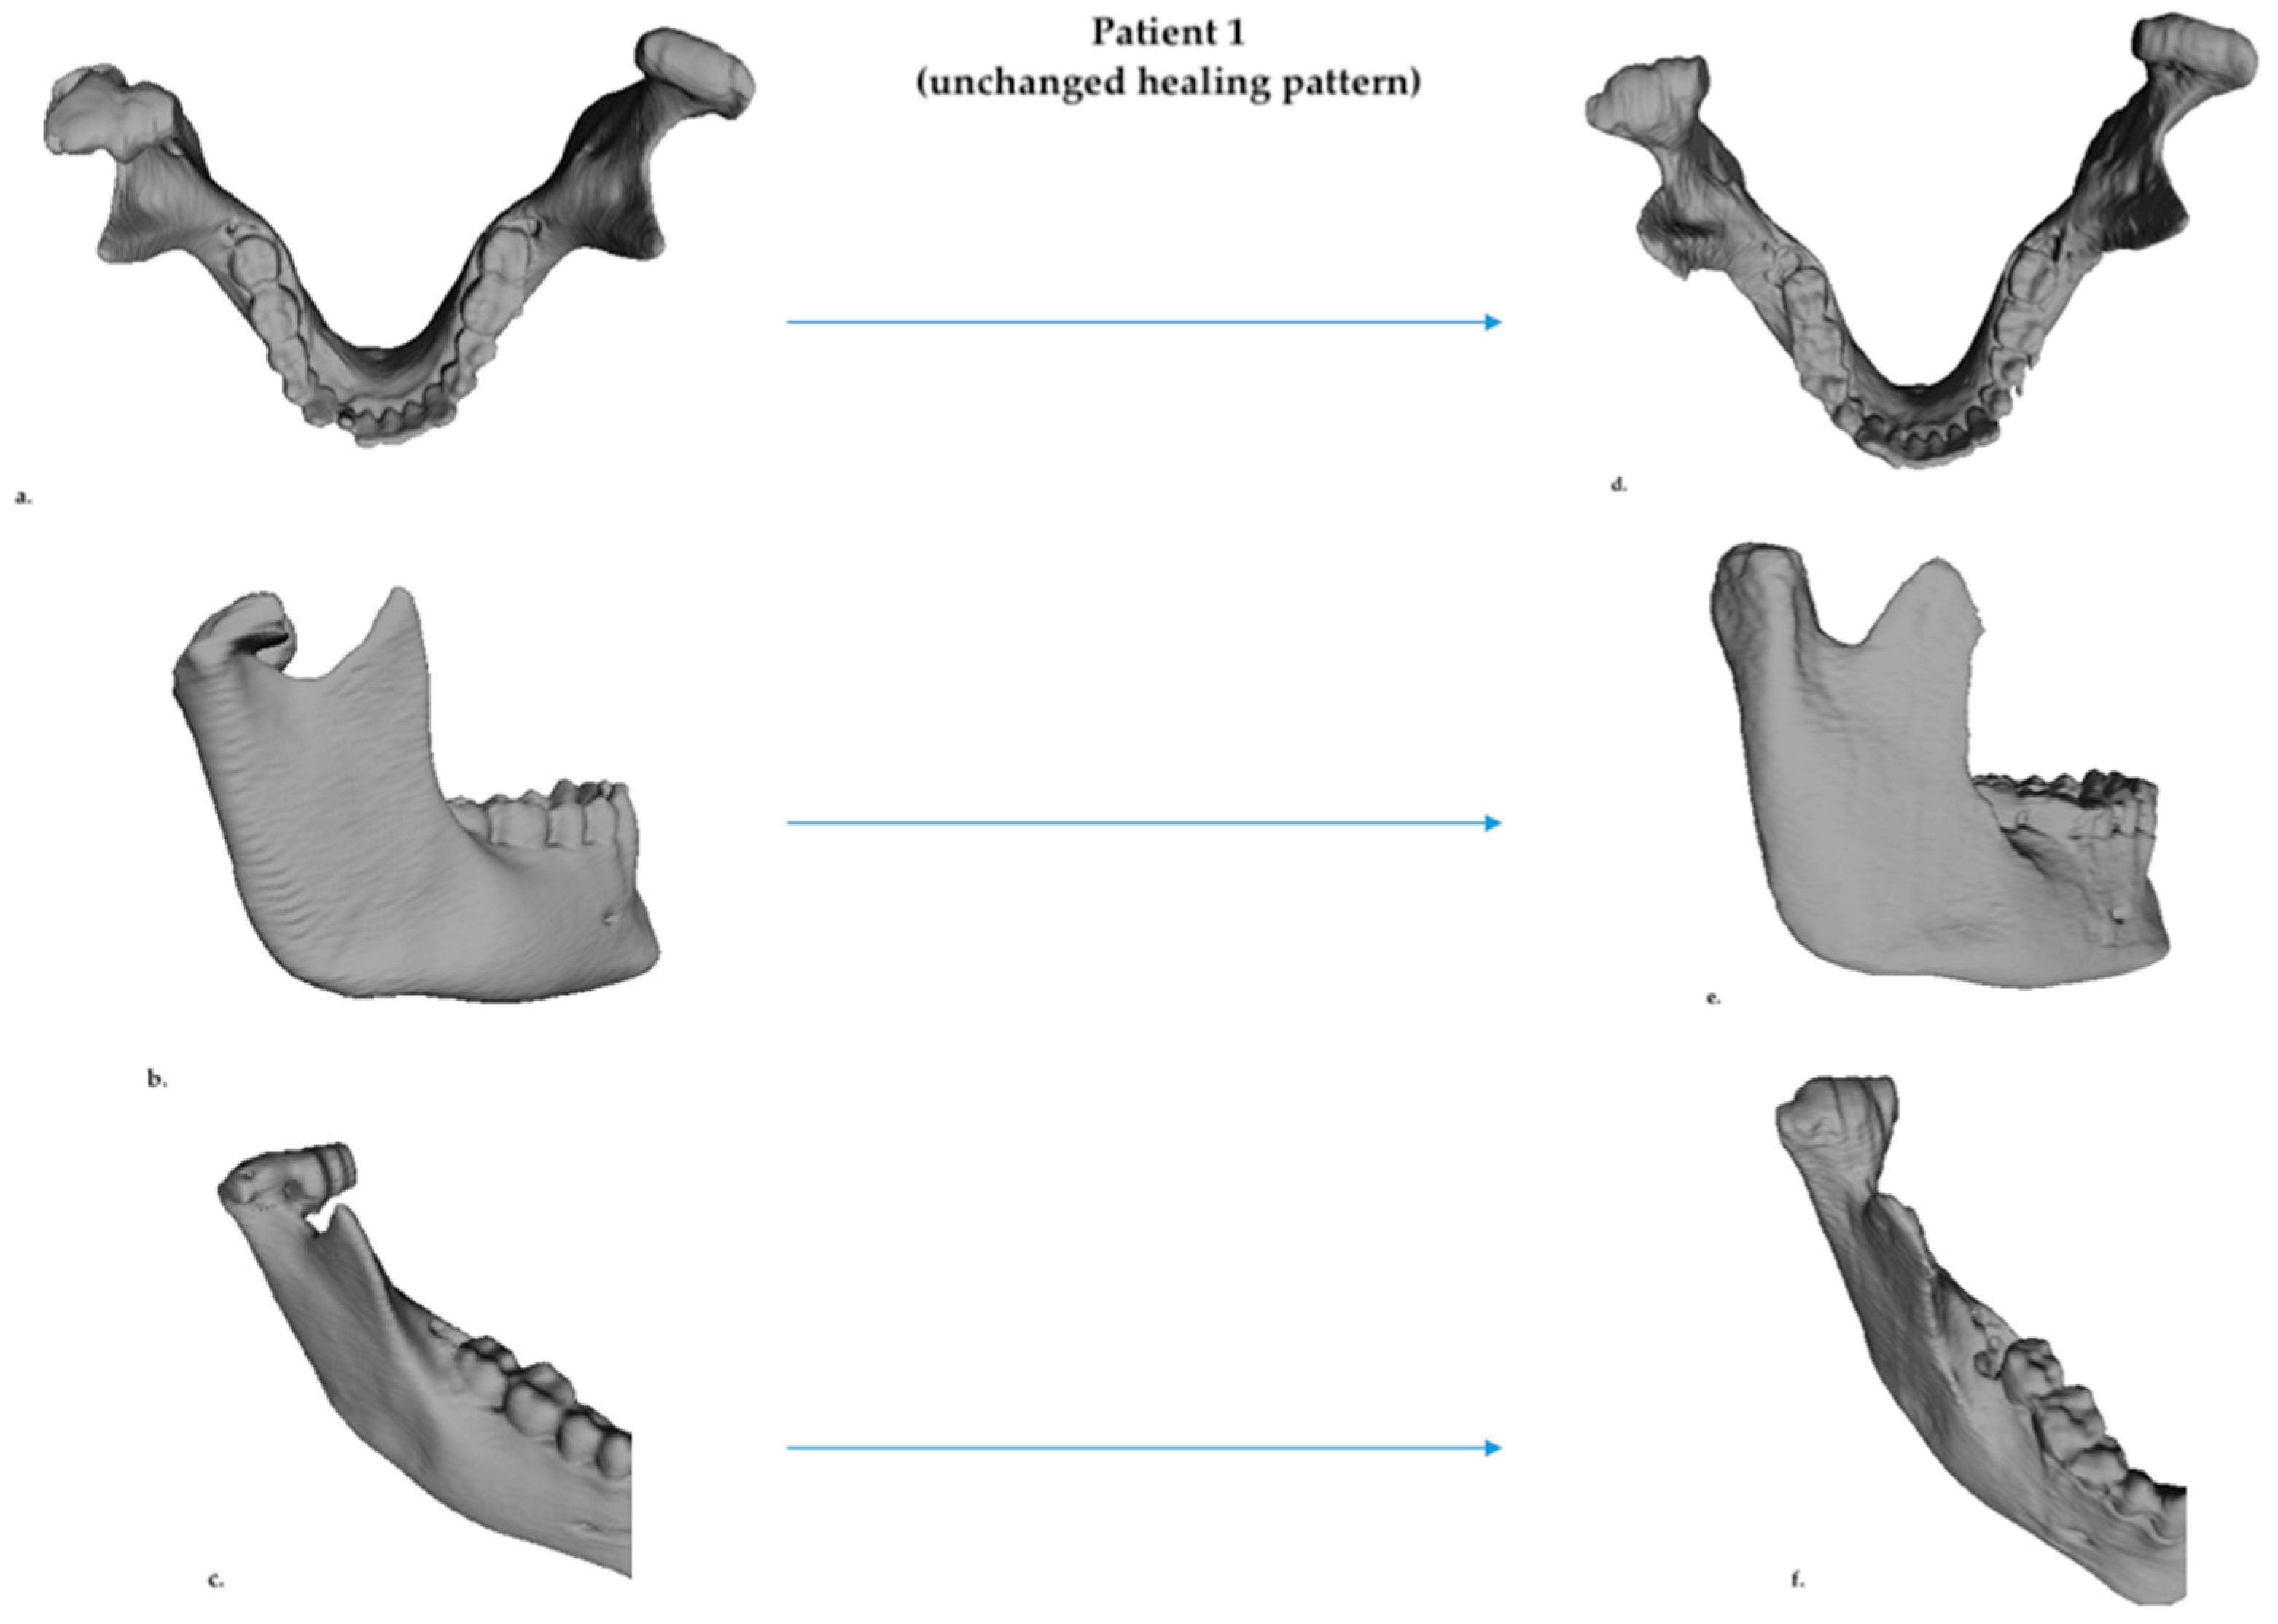

3.1. D Qualitative Assessment

3.2. D Skeletal Asymmetry Assessment